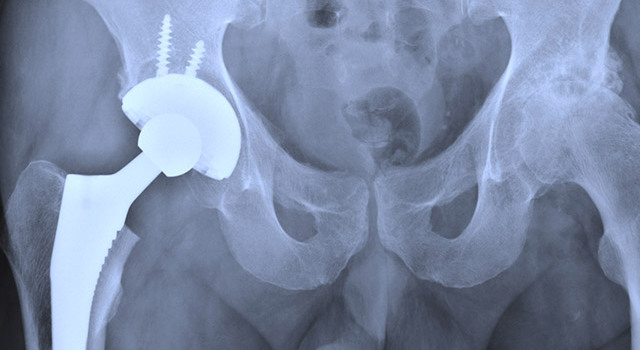

L’ANSM publie des recommandations concernant les prothèses de hanche totalement en métal car celles-ci pourraient bien se révéler dangereuses pour la santé.

Mi-décembre 2014, l’Agence de sécurité du médicament (ANSM) publiait des recommandations officielles qui déconseillaient la mise en place de prothèses de hanche à articulations métalliques, à cause d’un risque potentiel d'intoxication.

Et même si le comité scientifique européen n’a pas trouvé de risque général pour ce produit, l’Agence de sécurité du médicament conseille toutefois aux praticiens orthopédistes « d’éviter l’ensemble des prothèses de hanche à couple de frottement métal-métal chez les femmes en âge de procréer [et] les patients allergiques à des métaux ».

Il existe d’ailleurs, d’autres types de prothèses de hanche utilisant par exemple des couples inox-polyéthylène ou céramique-céramique (I. Céram).